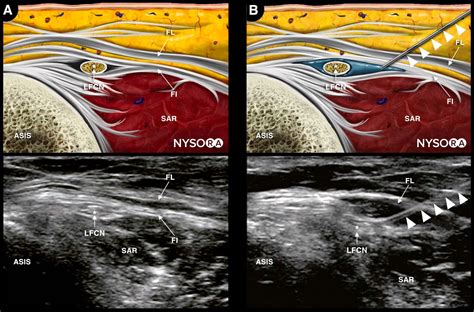

The ultrasound-guided technique has become the gold standard for performing a Femoral Nerve Block. It provides real-time visualization of the femoral nerve and surrounding structures, reducing the risk of complications and improving the success rate. The steps are as follows:

2. Place the ultrasound probe transversely over the inguinal crease to visualize the femoral nerve, artery, and vein.

3. Identify the femoral nerve, which appears as a hyperechoic structure lateral to the femoral artery.

4. Insert the needle in-plane with the ultrasound probe, aiming for the femoral nerve.

5. Aspirate to ensure the needle is not in a blood vessel, then inject the local anesthetic while visualizing the spread of the anesthetic around the nerve.

📌 Note: Ultrasound guidance requires specialized training and equipment but offers significant advantages in terms of accuracy and safety.